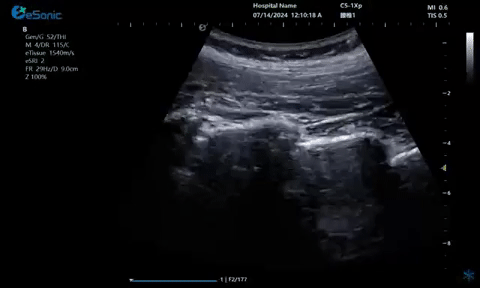

超声引导下蝶颚神经节阻滞术

大雁征-上颌动脉切面